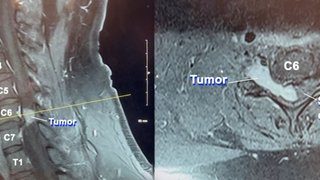

'Every day is a blessing': 11-hour surgery removes dangerous, rare spinal tumor

Charles Lavender says the 11-hour surgery to remove a rare cervical tumor that was pressing on his spinal cord saved his life.